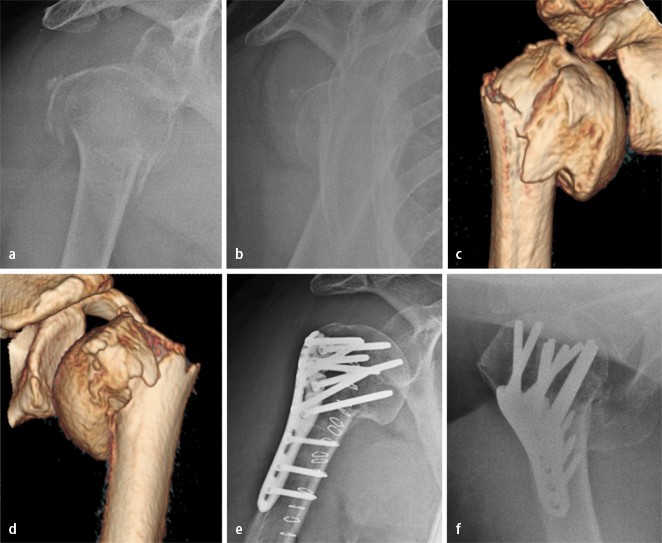

Posttraumatische Korrekturen und Revisionen bei proximaler Humerusfraktur | Trauma und Berufskrankheit

Korrektur-Osteotomien am Humerus nach Trauma | ATOS NEWS